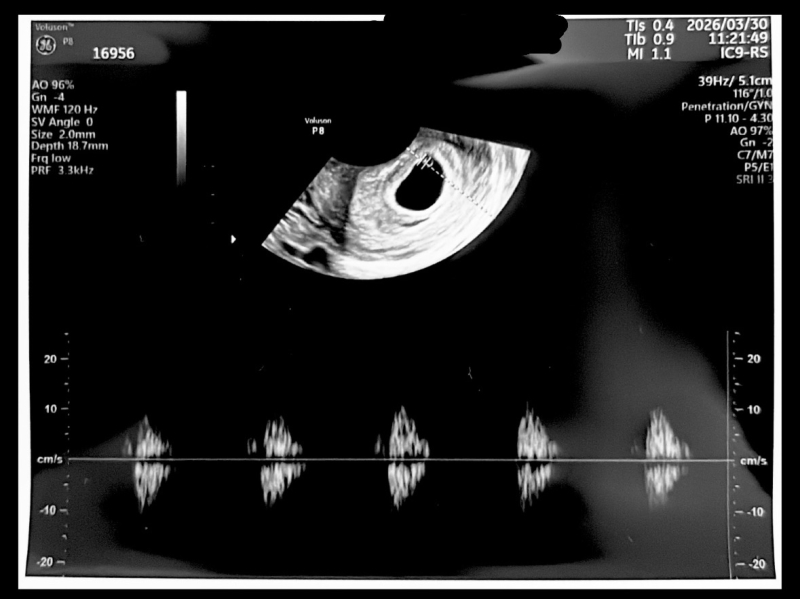

初めまして、初めての妊娠で不安なことだらけです。前回の生理開始日が2/6でそのまま計算するといま7週4日です。昨日初めて受診して赤ちゃんの大きさが3.2mmで心拍も他の方と違うのかな〜とずっと心配です。病院の先生には順調と言っていただけたのですが心配なので教えて頂きたいです。

現段階としては、3.2mm許容範囲のサイズ感であり、すでに、赤ちゃんの心拍が確認できていますから、そこが最も重要な発育評価になります。